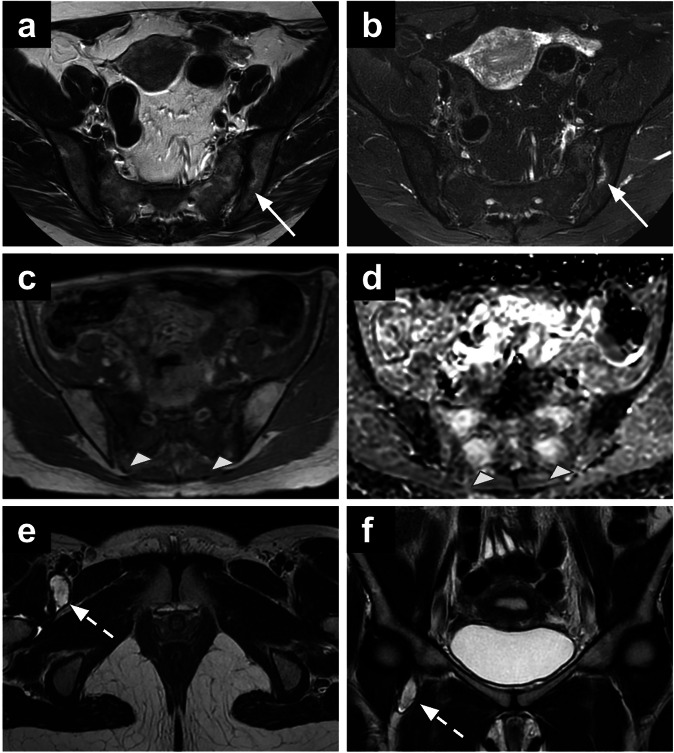

女性骨盆MRI的偶然发现给诊断带来了挑战,并可能具有重要的临床意义。定义为与主要影像学指征无关的异常,随着MRI在妇科实践中的广泛应用,这些发现变得越来越普遍。标准的妇科MRI方案,包括T1和t2加权序列,弥散加权成像和对比增强序列,促进了许多妇科外异常的特征,从良性到严重病变。这篇综述提出了一种基于区隔的方法来识别妇科外的发现,讨论他们的影像学特征和鉴别诊断。这种方法可以帮助放射科医生系统地评估偶然发现,潜在地提高对临床相关异常的认识,并支持及时的临床决策。关键相关性声明:骨盆MRI附带的妇科外发现可能会带来重大的诊断挑战。系统评估骨盆MRI附带的妇科外发现可以提高放射科医生对临床相关异常的认识。重点:骨盆MRI的妇科外偶然发现是常见的,范围从良性到恶性。基于腔室的分类——将女性骨盆分为前腔室、侧腔室、后腔室、肌肉骨骼腔室和其他腔室——为解释骨盆提供了一个系统的框架。全面评估所有MRI序列,包括大视场图像,可能有助于确定临床相关的偶然发现。

Incidental findings on female pelvic MRI present diagnostic challenges and may have significant clinical implications. Defined as abnormalities unrelated to the primary imaging indication, these findings have become increasingly prevalent with the expanded use of MRI in gynaecological practice. Standard gynaecological MRI protocols, incorporating T1- and T2-weighted sequences, diffusion-weighted imaging, and contrast-enhanced sequences, facilitate the characterisation of numerous extra-gynaecological abnormalities, ranging from benign to critical lesions. This review proposes a compartment-based approach for identifying extra-gynaecological findings, discussing their imaging characteristics and differential diagnoses. This approach may help radiologists systematically assess incidental findings, potentially improving the recognition of clinically relevant abnormalities and supporting timely clinical decision-making. CRITICAL RELEVANCE STATEMENT: Incidental extra-gynaecological findings on pelvic MRI can present significant diagnostic challenges. Systematic evaluation of incidental extra-gynaecological findings on pelvic MRI can improve radiologists' awareness of clinically relevant abnormalities. KEY POINTS: Extra-gynaecological incidental findings on pelvic MRI are common and range from benign to malignant conditions. A compartment-based classification-dividing the female pelvis into anterior, lateral, posterior, musculoskeletal, and miscellaneous compartments-provides a systematic framework for interpretation. Thorough assessment of all MRI sequences, including large field-of-view images, may help identify clinically relevant incidental findings.